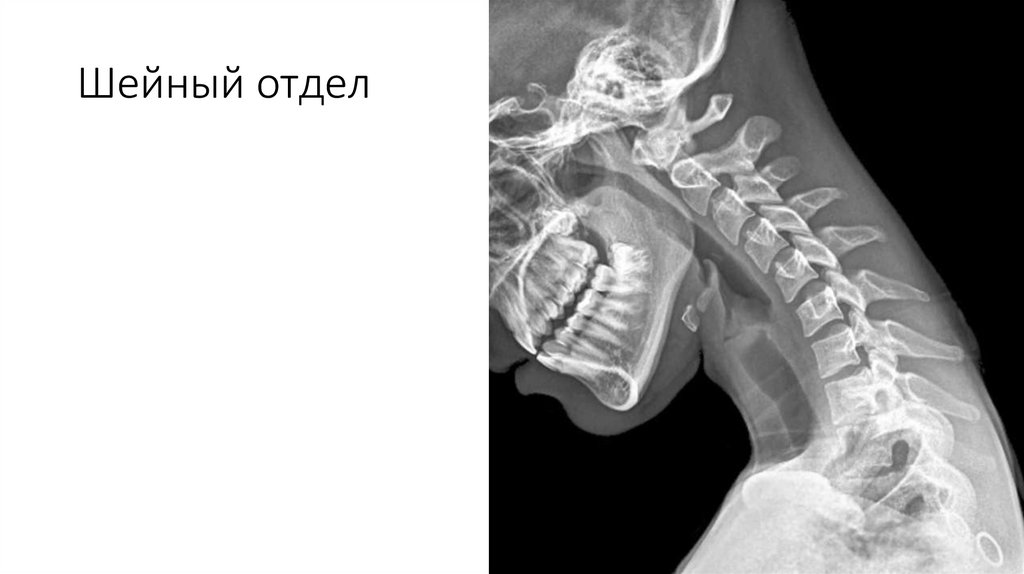

Шейный отдел